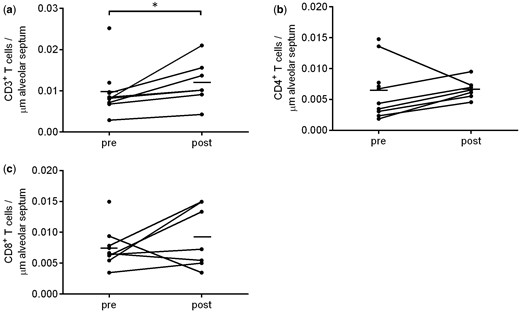

LVRS+BM-MSC輸注后,肺泡隔中CD3+T細(xì)胞的數(shù)量明顯高于之前 (?P=0.016) (圖4a )。

除一名患者外,所有患者在LVRS+BM-MSC輸注后,肺泡隔中CD4+?T細(xì)胞的數(shù)量均有所增加( P=0.30;按倍數(shù)變化計(jì)算P=0.047) (圖4b)